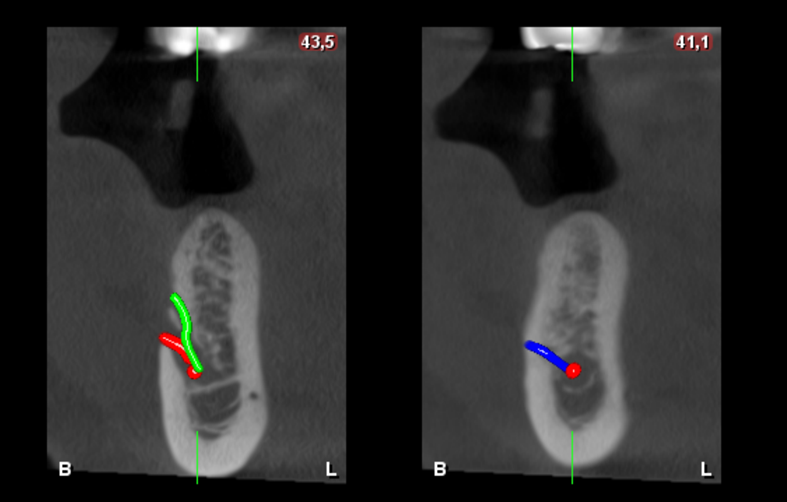

CORTES TRANSAXIALES

En la ampliación imagenológica con tomografía computarizada de haz cónico, a nivel del cuerpo mandibular derecho, se identifican forámenes accesorios adicionales al agujero mentoniano principal. Se observa un segundo agujero mentoniano de menor diámetro, ubicado superior al principal, con trayecto cefálico. Además, se identifica un tercer agujero mentoniano localizado en posición distal respecto al foramen principal.